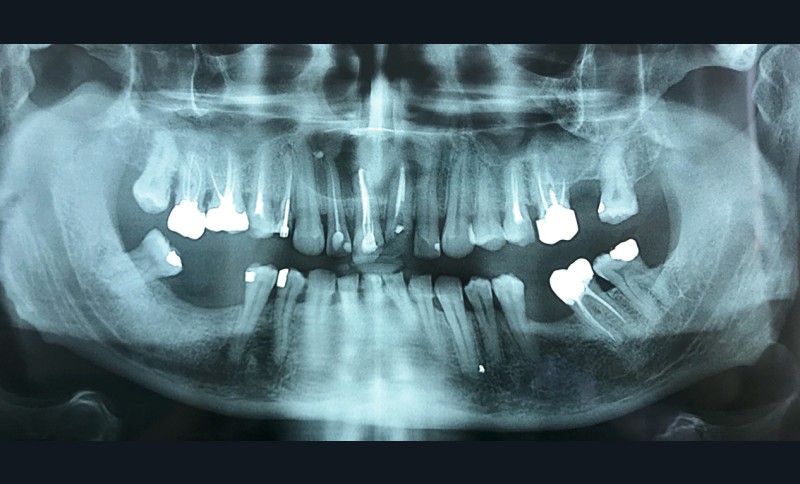

- Uni-loculaire (fig. 3), pouvant présenter un aspect caractéristique de « cœur de carte à jouer ».